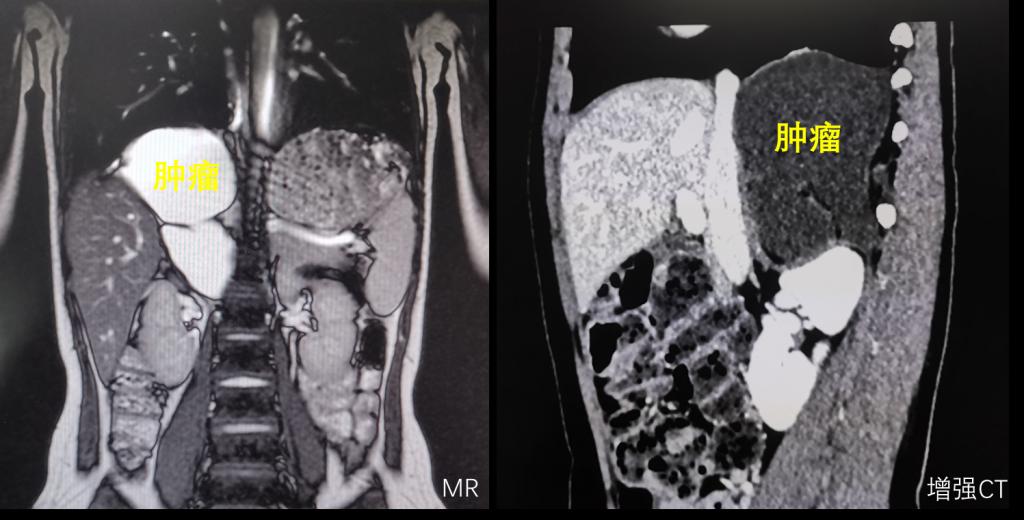

渭南某地10岁小姑娘因为间断性的腹痛到医院检查,意外发现腹腔内有一直径超过10cm巨大肿瘤。慕名来到我院小儿外科就诊。常规的超声检、磁共振和CT检查,都提示腹膜后有一个巨大肿瘤,而且这个肿瘤位置非常特殊,它长在肝脏、下腔静脉和腹主动脉等重要脏器和血管的后方,膈肌的下方,如果按照常规的手术思路,经腹手术,暴露困难,视野不佳,手术的难度和风险极大,而且只能是开放手术,创伤也会大大增加。

怎么样能够降低手术风险,也能够达到家属期望的微创治疗?经过多次讨论,鉴于肿瘤巨大及特殊位置,李鹏教授团队突破常规思维,提出经胸腔镜下切除腹膜后肿瘤的方案,利用胸腔空间大,切开膈肌后,暴露充分,手术的风险和难度反而大大降低,而且李鹏教授团队有丰富的胸腔镜操作的经验和技术,经过反复研究影像学资料和讨论,最终制定了胸腔镜下腹膜后肿瘤切除的方案及备选方案。